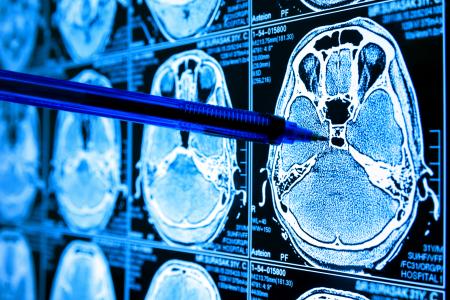

GLIOBLASTOME : L'antidépresseur suppresseur prometteur de tumeur

Un antidépresseur prometteur pour le traitement des tumeurs cérébrales, c’est l’espoir apporté par cette équipe de l’ETH Zurich qui ouvre ainsi une nouvelle voie thérapeutique pour lutter contre le glioblastome, un type de cancer du cerveau incurable et mortel. Ce criblage de médicaments à grande échelle, présenté dans la revue Nature Medicine, révèle ainsi que l'antidépresseur vortioxétine est l'un des agents les plus efficaces contre ce type de cellules cancéreuses.

Ces résultats ont déjà donné lieu à la planification d’essais cliniques à l'hôpital universitaire de Zurich. Car il est difficile de trouver des médicaments efficaces contre les tumeurs cérébrales, car la plupart des médicaments contre le cancer ne peuvent pas traverser la barrière hémato-encéphalique pour atteindre le cerveau. Cela limite le choix des options possibles. Les neuro-oncologues recherchent donc de meilleurs médicaments capables d’atteindre le cerveau et d’éliminer la tumeur.

Notamment le glioblastome, une tumeur cérébrale particulièrement agressive, aujourd’hui incurable. Les cancérologues peuvent prolonger l'espérance de vie des patients grâce à des opérations, des radiations, une chimiothérapie ou des interventions chirurgicales. Cependant la survie moyenne reste de 12 mois après diagnostic.